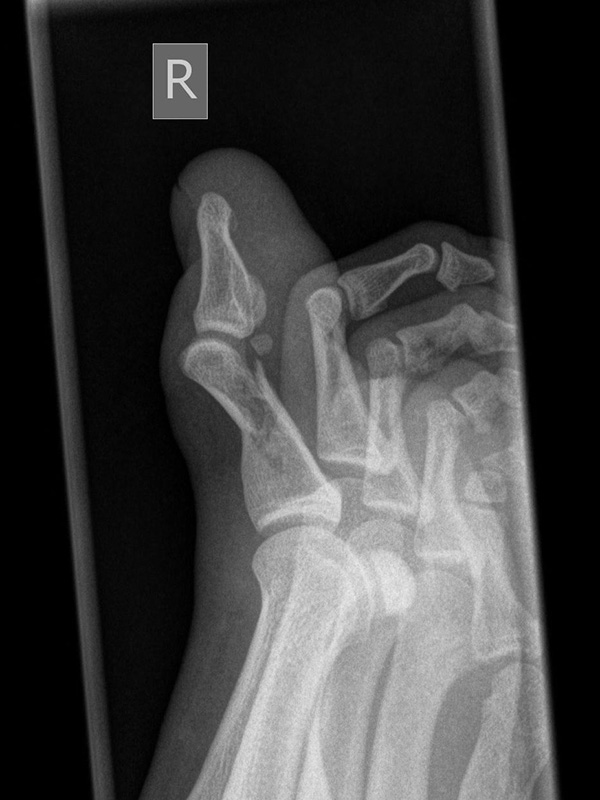

Zehe schräg

Positionierung:

• Der Patient sitzt auf dem Untersuchungstisch.

• Der Fuß steht auf der Kassette, der laterale Fußrand wird um 45° angehoben (Optional Verwendung eines Keilkissens).

• Der Zentralstrahl wird auf das Großzehengrundgelenk zentriert.

• Die anderen Zehen können zur Vermeidung von Überlagerungen mit einer Binde zur Seite gezogen werden.

• Die Röhre ist 0° vertikal ausgerichtet.

Kennzeichen des Röntgenbildes:

• Dorsoplantare Darstellung des Großzehengrundgelenks.

• Beurteilt wird der Abstand der Sesambeine zur Grundphalanx, insbesondere im Vergleich zu der Aufnahme ohne Dorsalextension.

Besondere Bemerkungen zum Beispielbild:

• Großzehe schräg bei Grundgliedfraktur mit diaphysäre Trümmerzone.

• Die Dislokation ist in der Schrägaufnahme gut erkennbar.

• Sesamoid im Ansatzbereich der Flexor hallucis longus Sehne.